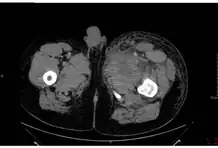

Inhalational anthrax, mediastinal widening

Possible edema and necrosis in a case of injection anthrax.